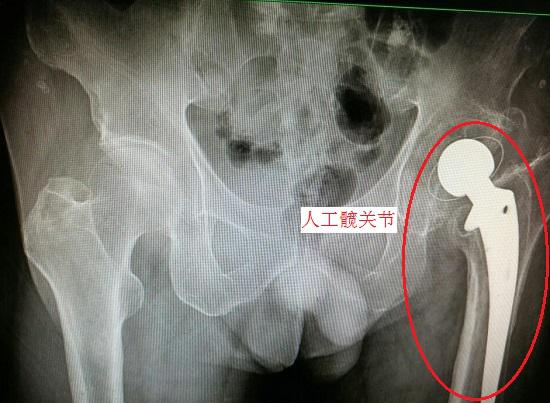

在众多骨骼中,髋部骨折发生概率较高,危害性也几乎最大(常被称为“人生最后一次骨折”,髋关节骨折后长时间卧床容易诱发肺部、泌尿系统感染、皮肤溃烂、静脉血栓等病症,一年内死亡率高达20%-30%),若能防患于未然,就能减少很多痛苦和悲剧。